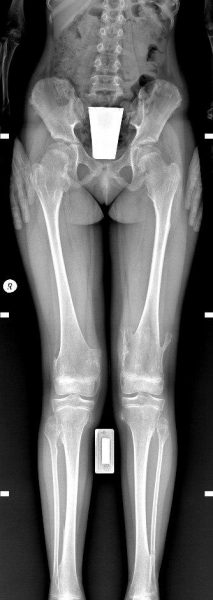

- Рентген, рентгеноскопія: Створює двовимірне зображення кісток. Швидкий та простий метод, але показує не всі деталі.

Рентген, рентгеноскопія: Швидкий та доступний для виявлення переломів, вивихів та інших проблем з кістками.

РЕНТГЕНОГРАФІЯ